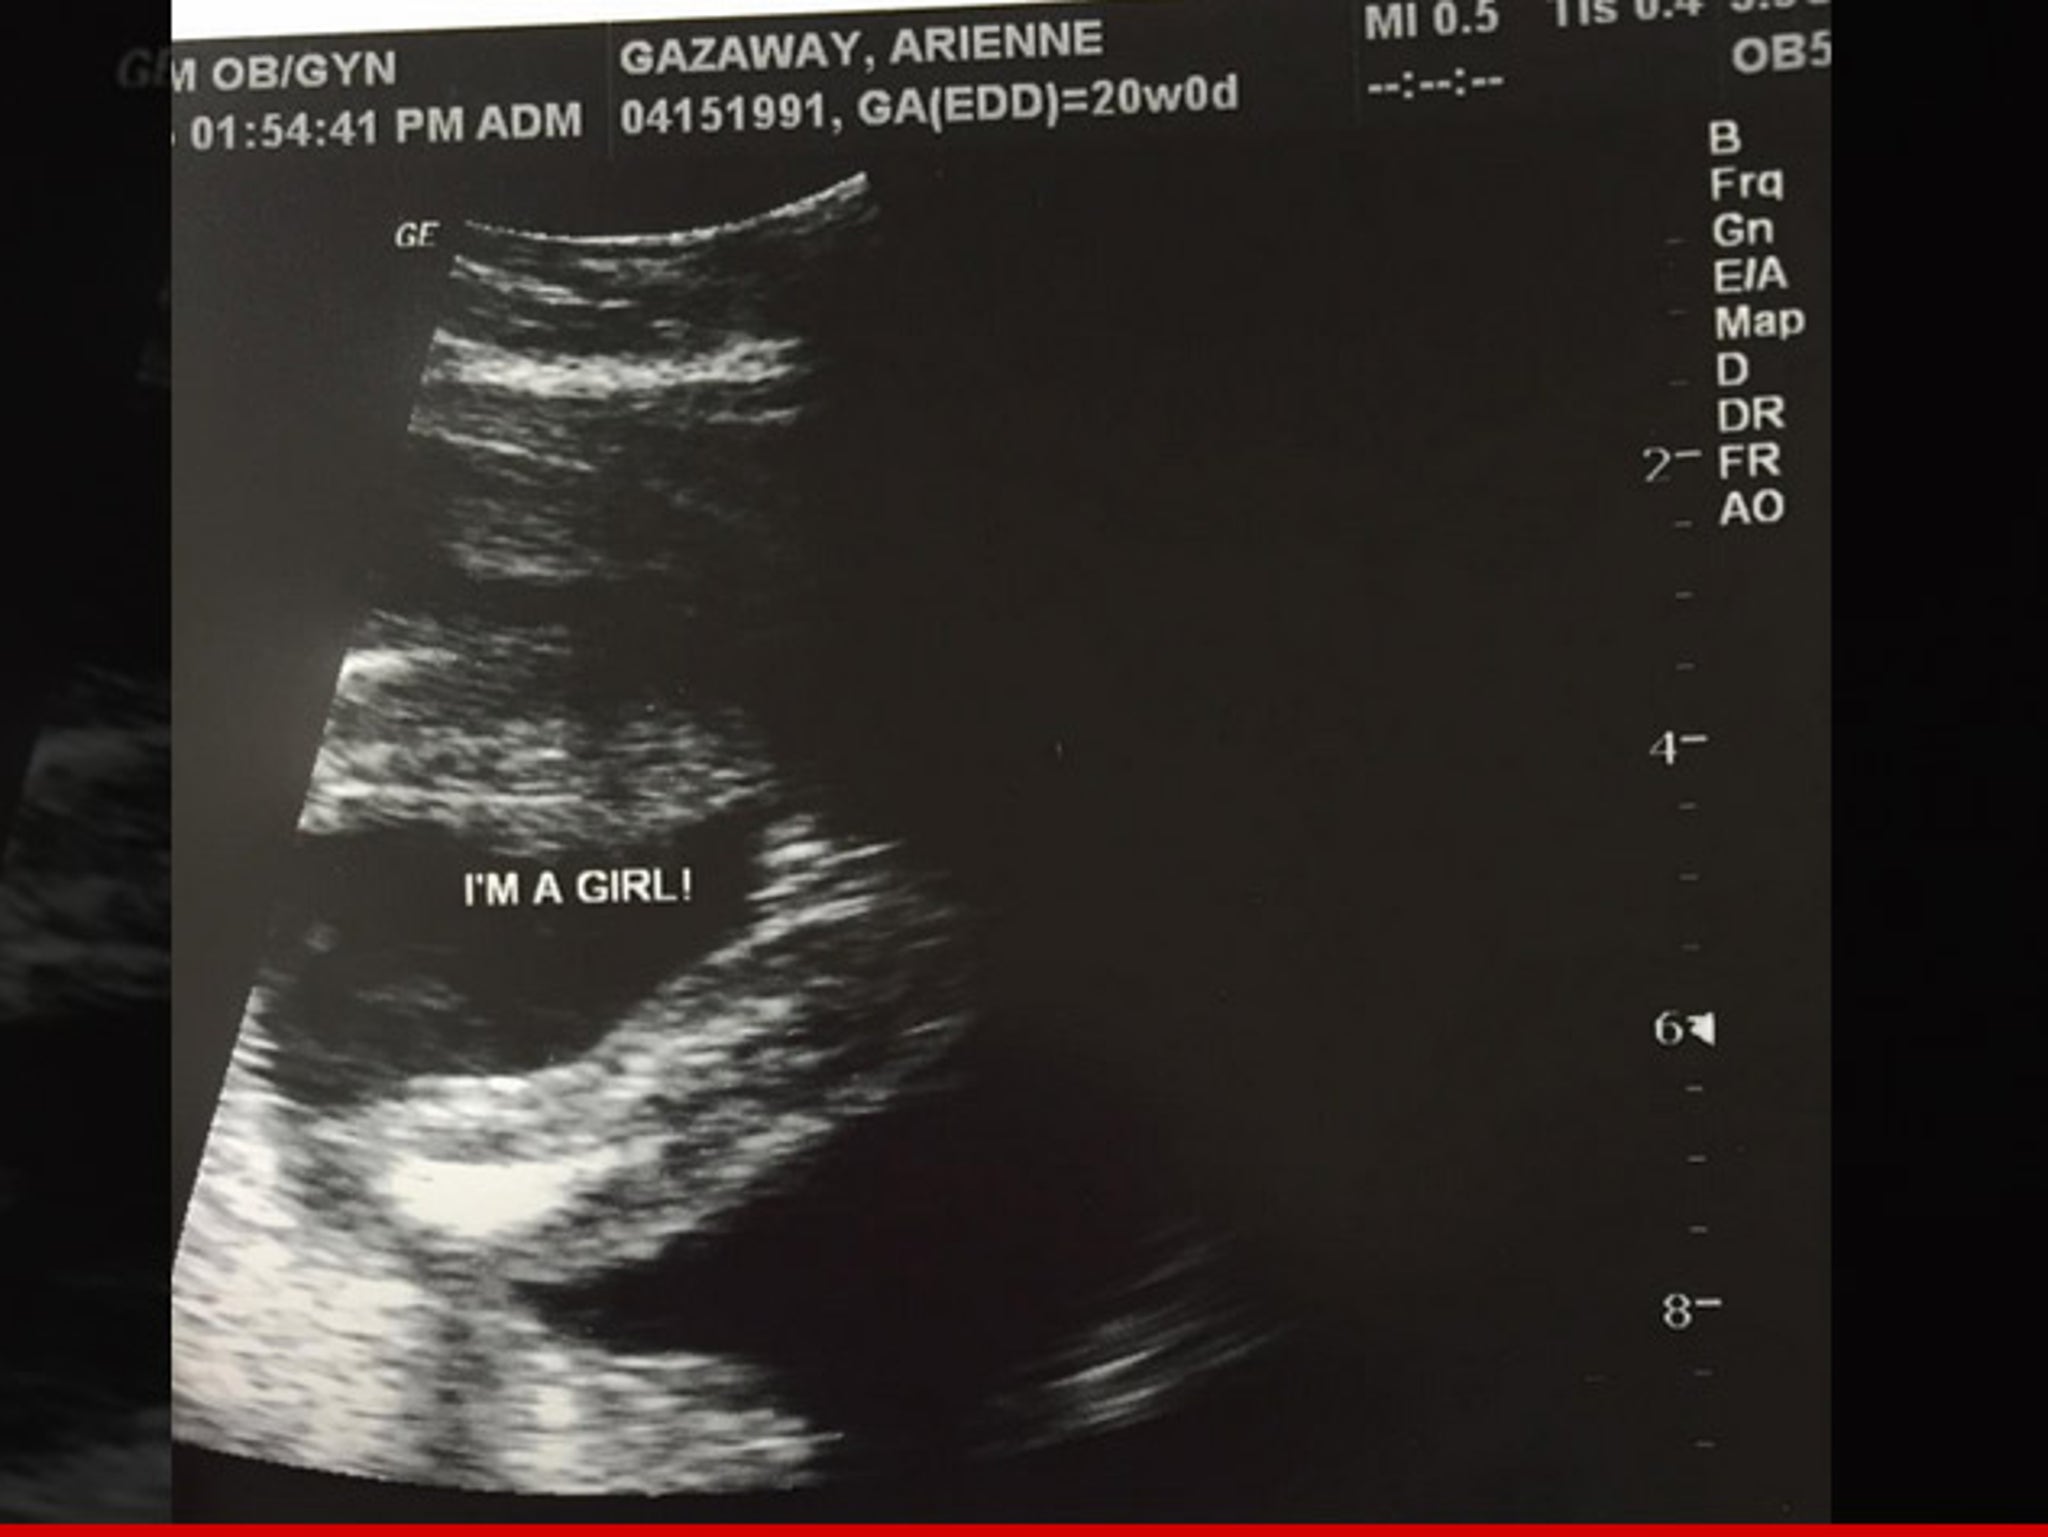

Adrien Broner My Chick S Pregnant With My 7th Baby